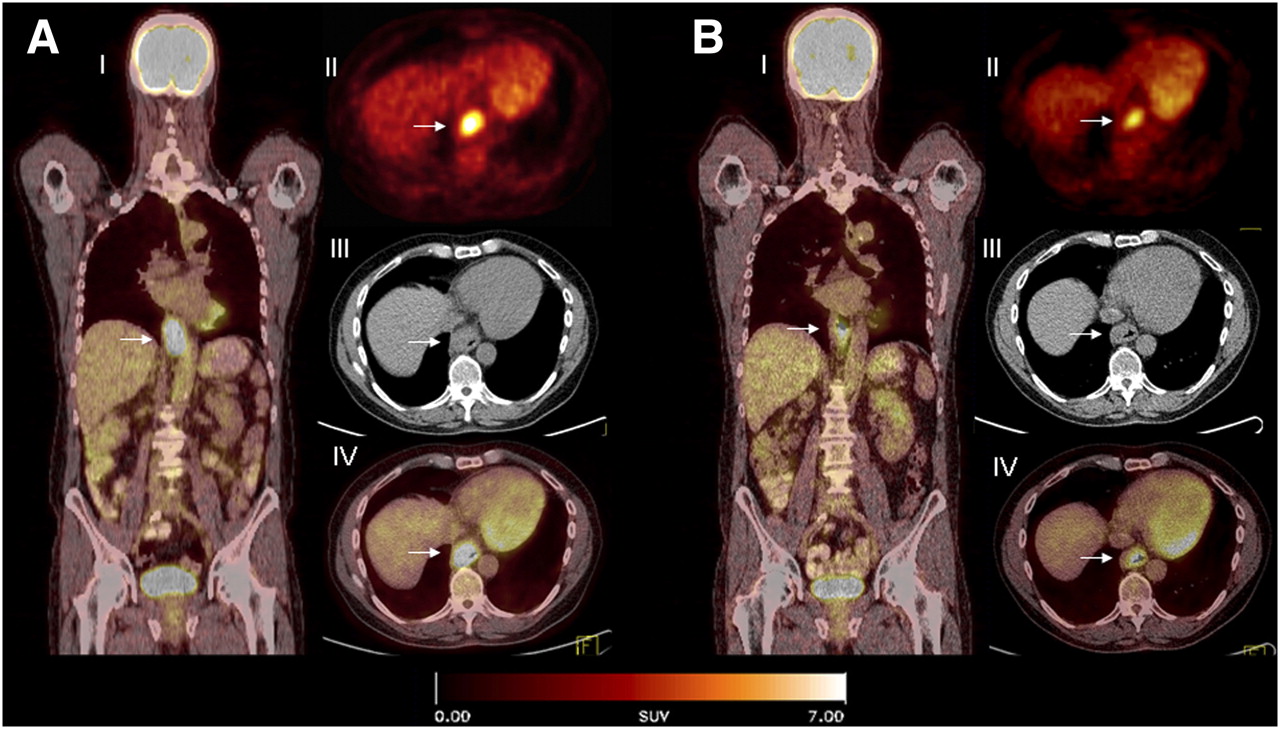

Panel Of 18 F FDG PET CT Imaging At 6 Months Follow up Of Patient 7

https://www.researchgate.net/profile/Brunolf_Lagerveld/publication/286478657/figure/download/fig6/AS:306456508289029@1450076333191/Panel-of-18-F-FDG-PET-CT-imaging-at-6-months-follow-up-of-patient-7-There-are-2-FDG-avid.png